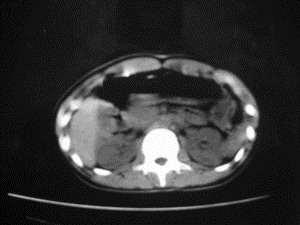

患者女,20岁,被车撞伤3小时,pe:全腹肌紧张,压痛反跳痛,以右上腹为著,肠鸣音减弱。有手术结果。![]() ![]() ![]() ![]() ![]() ![]() ![]() ![]() ![]() ![]() ![]() ![]() ![]() ![]() ![]() ![]() ![]() ![]() ![]() ![]() ![]() jiajie发言: ![]() 考虑空腔脏器穿孔。 dyqct发言:考虑:1、肝左叶外侧段断裂伤伴少量腹血。2、空腔脏器穿孔。 fangzheng发言:仅见腹腔内游离气体,提示空腔脏器穿孔。 guoke发言:胃内密度增高,肠腔内充满气体,考虑肠腔破裂出血 mmg94发言:胃后壁见一增厚软组织密度影,肝左叶前见游离气体影,左腹腔内局部肠管壁、系膜增厚。并见类圆形软组织。以上征象提示消化道管腔破裂,小肠、肠系膜挫裂伤,腹腔血肿形成。 拾荒者发言:肝实质密度不均匀,胃内见不均匀高密度影。考虑:肝挫裂伤,胃内应激性溃疡出血。 守望可可西里发言: 以下是引用jiajie在2006-6-20 15:49:00的发言:[br] [br][br]考虑空腔脏器穿孔。jiajie老师,我鼓起了很大的勇气才决定给您唱个反调儿,如果我错了,请您一定给我指出来,谢谢您了。我反复看了解剖图谱,觉得您所说的“考虑空腔脏器穿孔”上图所用箭头标明的不是游离气体。请您看以下几幅图片: ![]() ![]() ![]() ![]() ![]() ![]() ![]() ![]() 再请您看向医生老师发表的解剖图谱3幅 ![]() ![]() ![]() 这以下几幅图,我认为是肝包膜下积血。不过,说实在话,我没有发现有明显的肝挫裂伤。不对的地方请您一定指出来,再次感谢您了,jiajie 老师! ![]() ![]() ![]() ![]() 这下面几幅图片,我认为有明显的左中上腹部小肠损伤。 ![]() ![]() ![]() ![]() ![]() ![]() ![]() ![]() jiajie 老师,估计我说的是错误的,但我实在闹不明白,请您一定不要笑话我,并指出我的错误,以便于我减少工作中的失误。再次感谢您了,jiajie 老师! 至于胃内的不均匀高密度,我认为拾荒者战友说的有道理,胃内应激性溃疡出血和胃内容物混合所致。 手术结果:左肝叶(iv段)前缘长约8cm挫裂伤口,舌叶根部下< |